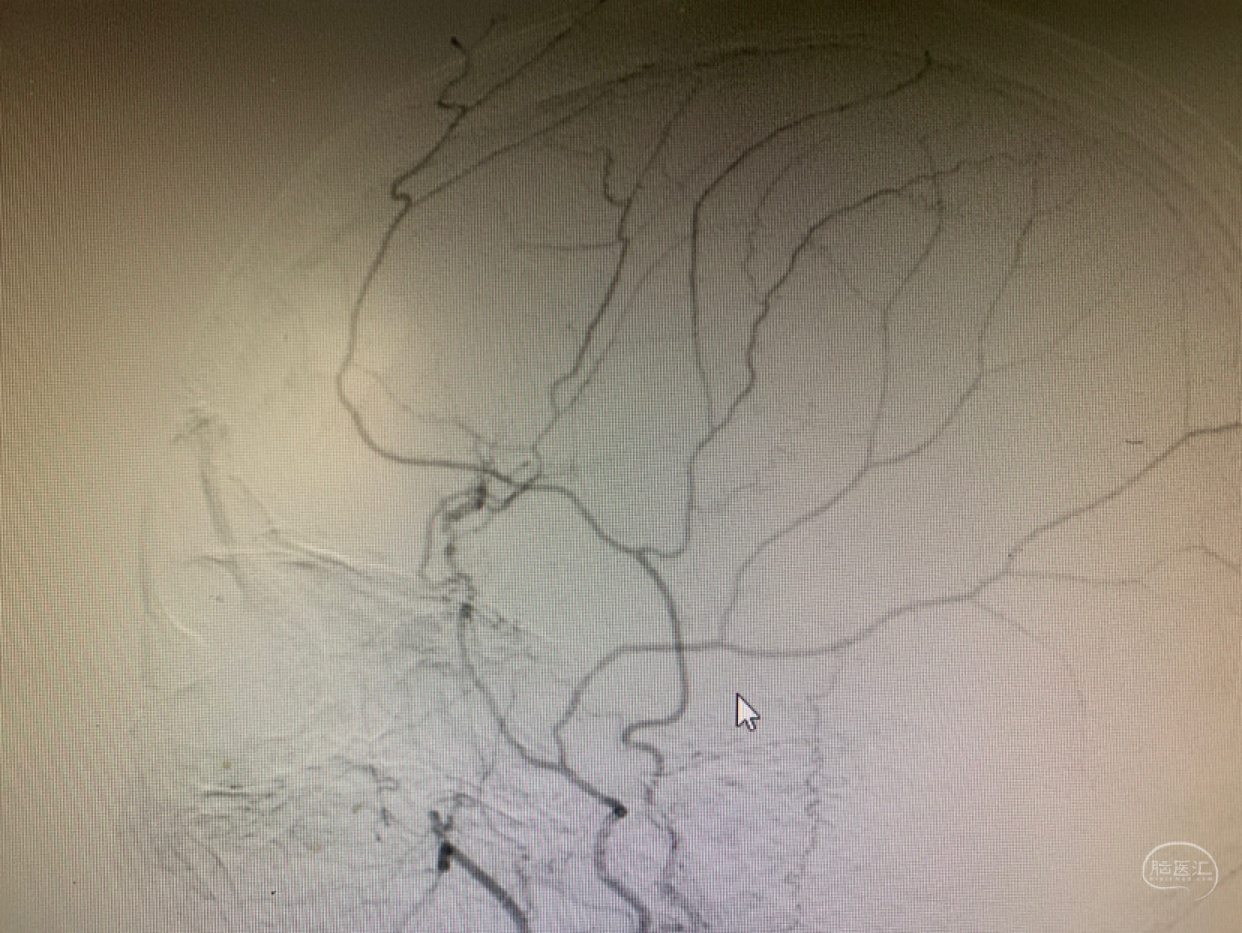

DSA(颈内造影)

DSA(颈外造影)